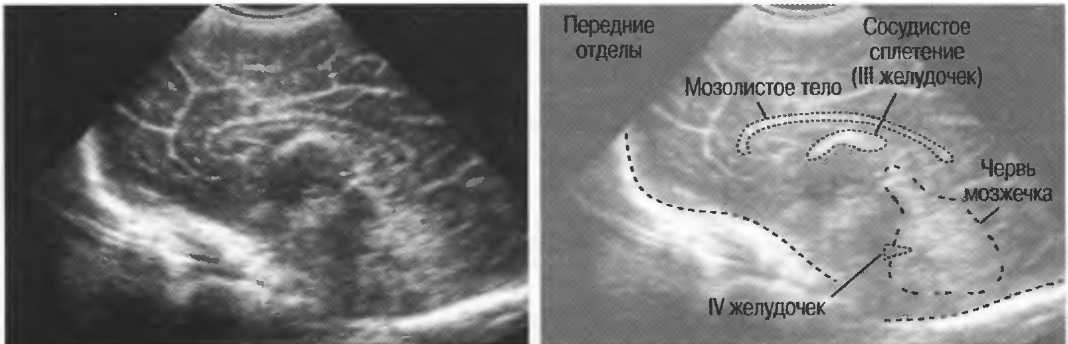

3. Ультразвуковые исследования в педиатрии. Для детей необходим датчик с частотой 5 МГц с глубиной фокусировки на 5-7 см. При исследовании мозга новорожденного используется секторный датчик с частотой 7,5 МГц с глубиной фокусировки на 4-5 см (этот датчик также используется для исследования яичек и структур шеи у взрослых).